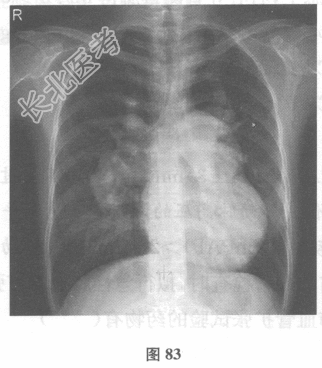

- 多项选择题2.(提示:胸部X线片见图83。)为进一步诊断, 下一步最应检查( )

- 多项选择题3.(提示:血清学及免疫学检查无明显异常, 动脉血气分析提示呼吸性碱中毒。超声心动图:右心房、右心室内径增大, 右房室瓣相对关闭不全,右心室前壁及室间隔增厚, 肺动脉收缩压93mmHg。肺功能:轻度限制性通气障碍。胸部CT、肺通气/灌注显像、腹部超声检查均无异常。拟诊为特发性肺动脉高压, 行右心导管检查。)肺动脉高压的诊断标准是( )